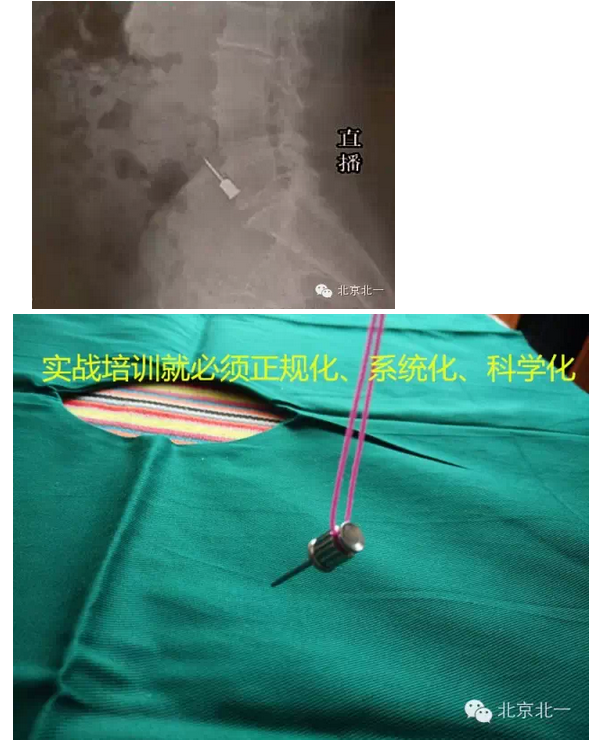

9關(guān)鍵一條,螺絲刀未纏線。容易誤吸或者誤吞(預(yù)防措施就是:在種植啟蒙教育階段強(qiáng)調(diào)栓繩子,實(shí)戰(zhàn)演練時(shí)就要形成良好習(xí)慣)

10關(guān)鍵第二條,強(qiáng)吸不到位,吸力不夠。(王老師認(rèn)為:強(qiáng)吸到位,手術(shù)就成功了一半)慢慢體會(huì)吧。